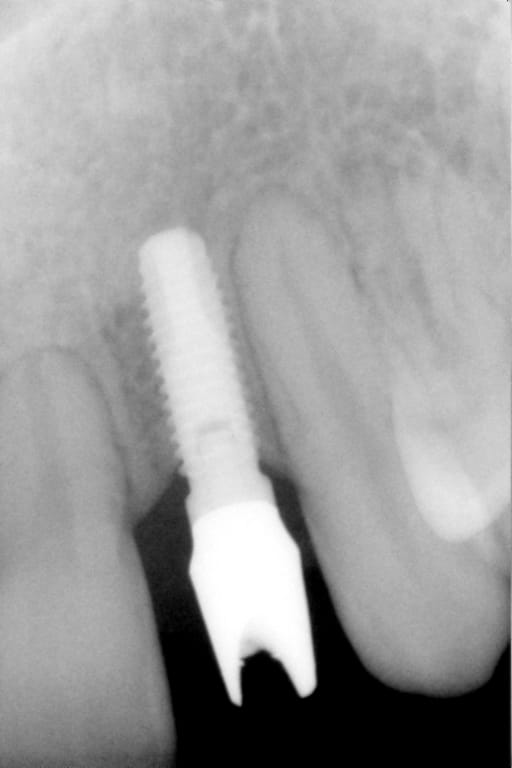

On m'a dit que Pluton était incollable sur les implants.

Alors, j'aimerais demander à Pluton s'il sait ce que c'est...

dis m'en un peu plus sur ce cas car c'est un implant avec un hexagone externe et j'ai beaucoup de correspondances....

cela dit, hex externe en général c'est une plateforme standard et quasi toutes les marques sont compatibles

donc çà limite un peu les recherches sur les marques disponibles en france à cette époque et la marque d'implant qui match le plus avec les caractéristiques que tu m'as montré (hex externe, apex plat, spires en V, col large, vis de cicat avec hexagone....) c'est un implant Biomet 3i osseotite parallel walled